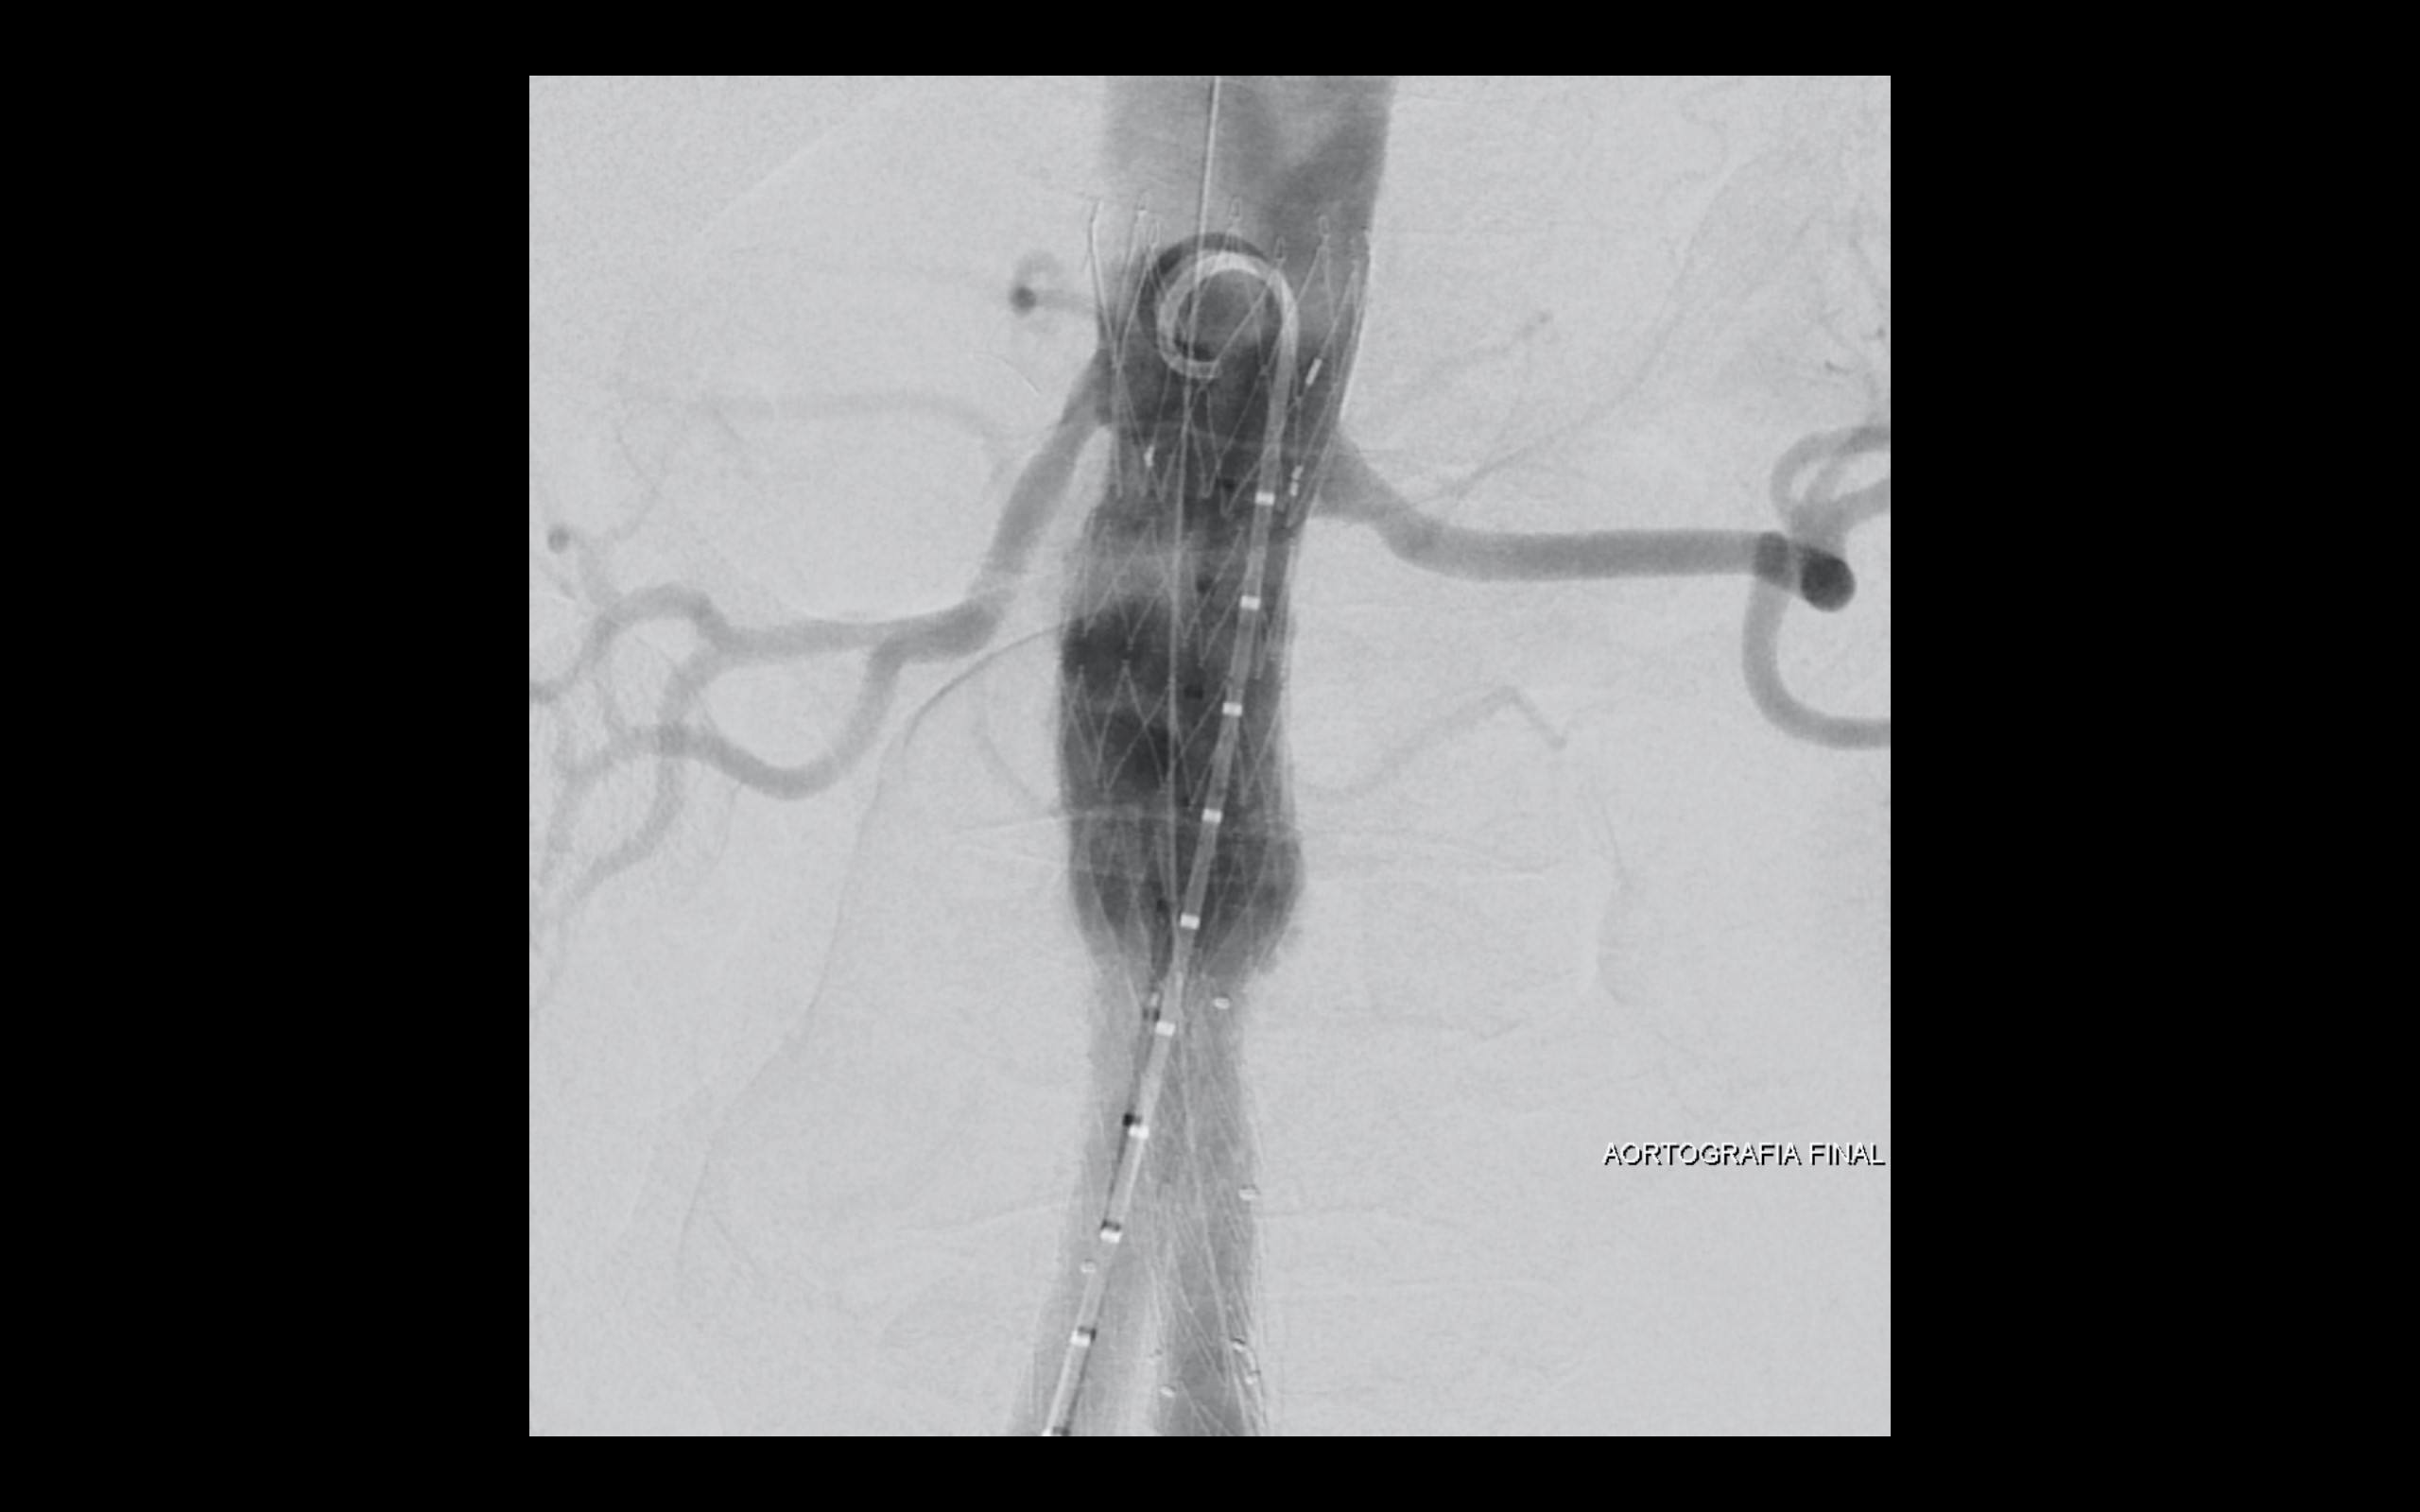

Optado diante do quadro clínico de dor pelo tratamento endovascular percutâneo com endoprótese de baixo perfil.